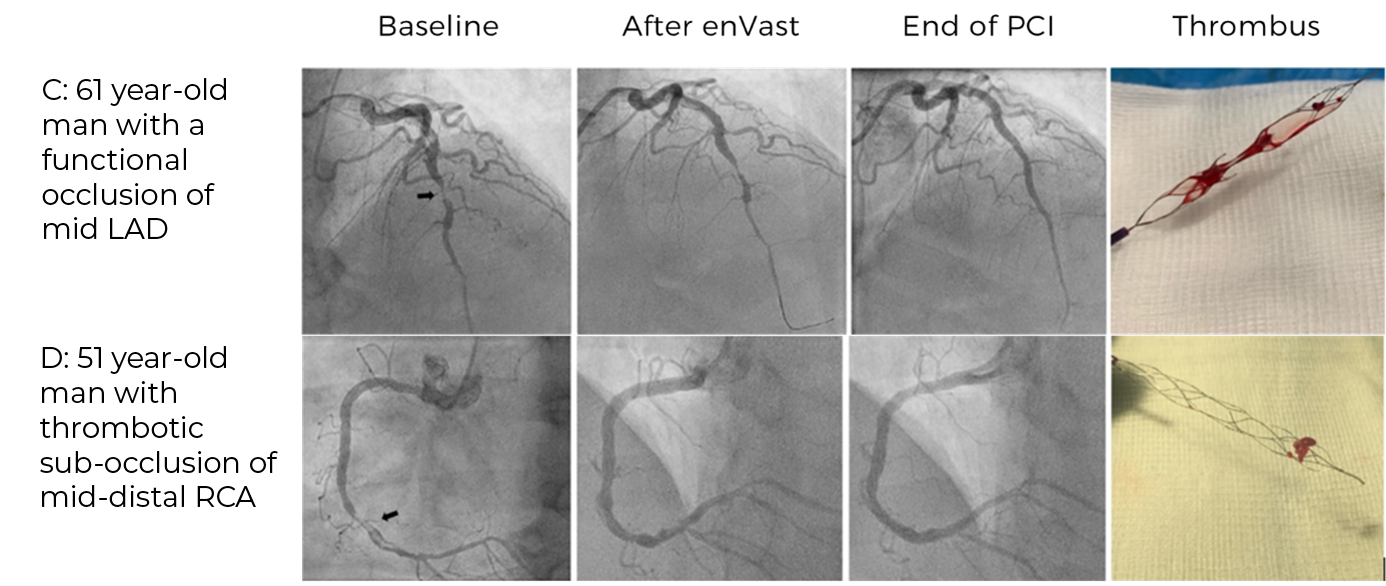

In a first-in-human case series of 61 STEMI patients with LTB, a thrombectomy technique with an enVast stent retriever and continuous aspiration was developed for coronary care.

The technique was safe and warranted high rates of successful flow restoration in culprit vessels​

Dr. Marco Vaglimigli, Deputy Chief of Cardiology at Cardiocentro Ticino Istituto, Switzerland, uses enVast in STEMI patients

enVast devices with freshly removed LTB clots inside